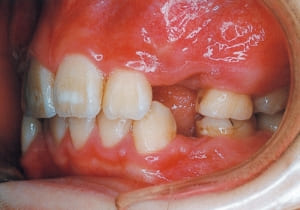

Age at initial visit : 7 y 7 m, male /Protruding upper bite. Open bite. Receding lower jaw. Protruding dual dentition.

3 Initial Visit 2-11-’88

4 Initial Visit 2-11-’88

The Class II condition is pronounced, with a significant overjet of 12.5 mm(3). Although the teeth size are large, crowding is relatively mild. The maxillofacial structure has good depth and a robust bone framework(5). The mandible itself is solid , robust gonial angle, but there is significant anterior-posterior displacement relative to the maxilla(ANB 10.0°). While there is no confirmed history of thumb-sucking or similar habits, the lower lip is already pushing up against the maxillary incisors. The cause of this condition is unknown.